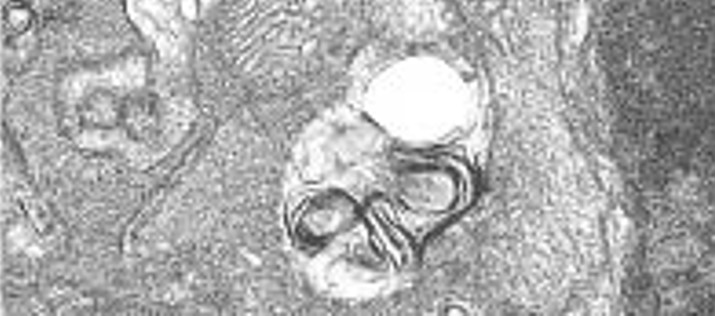

Imagen de microscopía electrónica mostrando los autofagosomas presentes en las retinas de ratones knock-out para Igf1.

Los resultados de este trabajo muestran que el ratón deficiente en Igf1 presenta una inflamación crónica en la retina que se ve atenuada mediante activación de la autofagia a los 6 meses de edad, pero que no es capaz de hacerlo a los 12 meses. El estudio proporciona evidencias que apuntan a que la autofagia podría proteger frente a la inflamación crónica de la retina durante el envejecimiento en un modelo de ratón deficiente en IGF-1. El trabajo ha sido publicado recientemente en Disease Models & Mechanisms. Disease Models & Mechanisms.